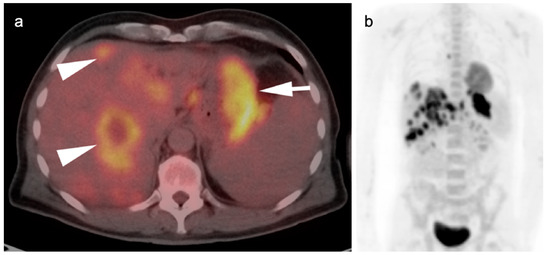

4. Hepatocellular Carcinoma